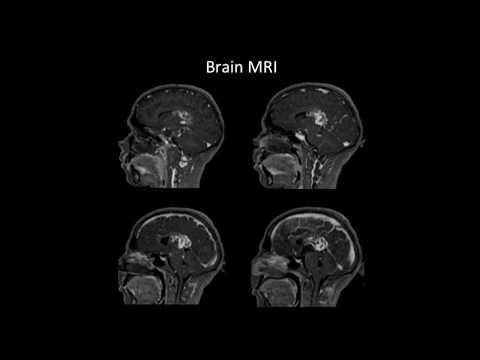

Hellow guys, Welcome to my website, and you are watching OZ Craniotomy Transsylvian-Transpeduncular Approach for Resection of an Anterior Midbrain AVM. and this vIdeo is uploaded by Barrow Neurological Institute at 2023-02-22T09:13:26-08:00. We are pramote this video only for entertainment and educational perpose only. So, I hop you like our website.